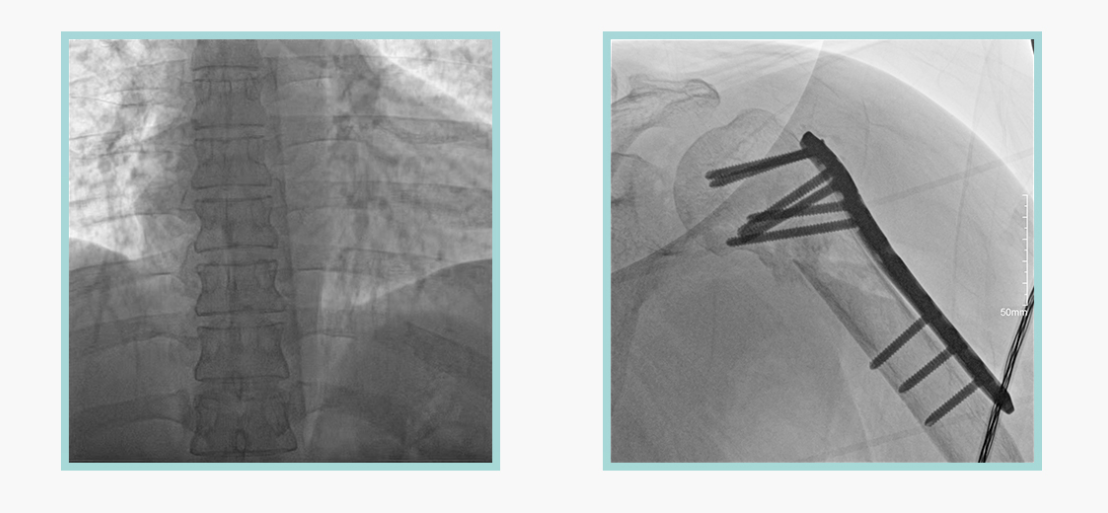

必一运动科技悦画移动C臂X线摄影系统,采用了业内技术最尖端的CMOS探测器。基于性能优异的针状CSI闪烁体涂层和高灵敏度的CMOS感光芯片,悦画可以实现在超低X线剂量条件下实现高清晰影像成像,相较于一般的影增移动C臂和平板C臂,动态范围更高,影像的层次感和对比度更好。

在产品的性能参数设计上,悦画的像素可达到200万,空间分辨率可达到3.2线对,采用16bit的影像灰度,悦画在影像后处理上,通过SPI金字塔图像算法,支持摄影、脉冲透视影像、连续透视等多种模式下的影像采集,动态透视影像视频支持保存与回放。双大屏的设计,透视影像支持三档放大,保证临床影像读取的便利。

悦画在影像的伪影处理上,也积累多项图像处理专利技术。通过对植入物的精准识别,悦画能够精准祛除植入物伪影与运动伪影,保证高质量的影像输出,无论是影像的对比度、分辨率(清晰度)相较于市面上的移动C臂产品都更胜一筹。